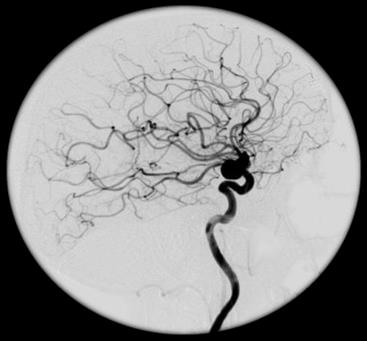

Na przekroju poprzecznym TK mózgu strzałką wskazano obszar

Ilustracja do pytania 17

A. hypodensyjny w płacie czołowym.

B. hyperdensyjny w płacie czołowym.

C. hypodensyjny w móżdżku.

D. hyperdensyjny w móżdżku.